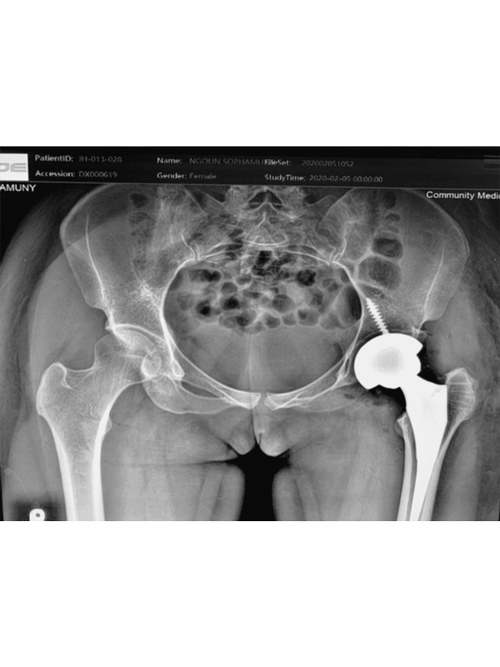

Dr. Weber and his partners participate in short term medical mission trips to Cambodia. Dr. Weber has had the pleasure of going twice now in 2018 and 2020. During these trips Dr. Weber performs total hip replacements on patients who normally would have no treatment options. To learn more and to see videos from the experience please click the links below.